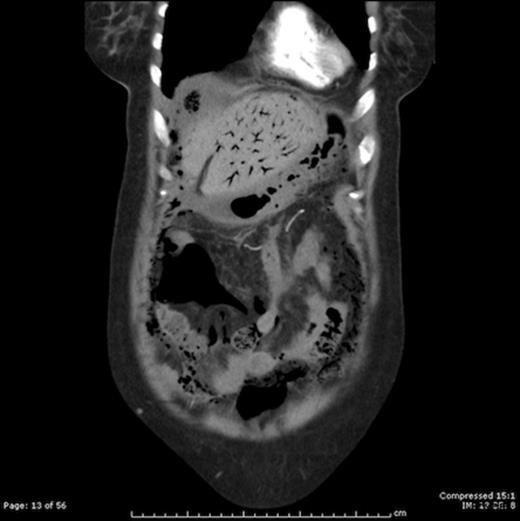

A 66 years old female presented with acute lower abdominal pain for 2 days. She had a background of hypertension and mesenteric angina. General examination revealed tachycardia and pallor. On abdominal examination, there was tenderness and rigidity in the lower abdomen with signs of peritonitis. Blood results included a CRP of 242, WCC 9.3, mildly elevated urea and creatinine levels, bilirubin 86 and evidence of metabolic acidosis and lactate of 4.2. CT scan revealed intestinal pneumatosis affecting the ileal loops, with free gas in the abdominal cavity and gas in the portal venous system, in keeping with acute ischemia and perforation involving ileal bowel loops (Figure 1 and 2)

CT scan showing portal venous gas and pneumatosis intestinalis in a large intraabdominal cystic mass (Gangrenous Meckel’s Diverticulum)